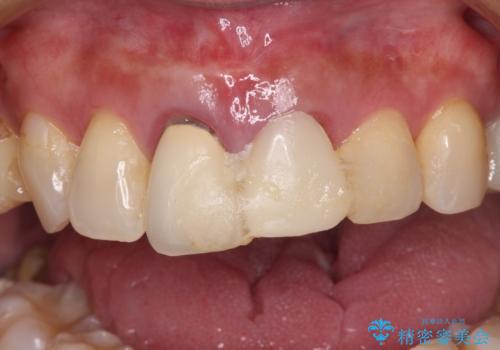

- 治療中の前歯の仮歯がひどい状態であるとのことで来院された患者様です。

治療中の前歯は根管治療の途中であり、根尖部に痛みを感じる状態でした。

まずは審美的な仮歯を装着し、根管治療を行った後にオールセラミッククラウンにて補綴治療を行うこととしました。

根管治療後に痛みは軽減しましたが、僅かな痛みが続くとのことで、レントゲン写真では病変は認められなかったものの、歯根端切除を行うこととしました。処置後は痛みは全くなくなり、安心して補綴治療を行うことができました。